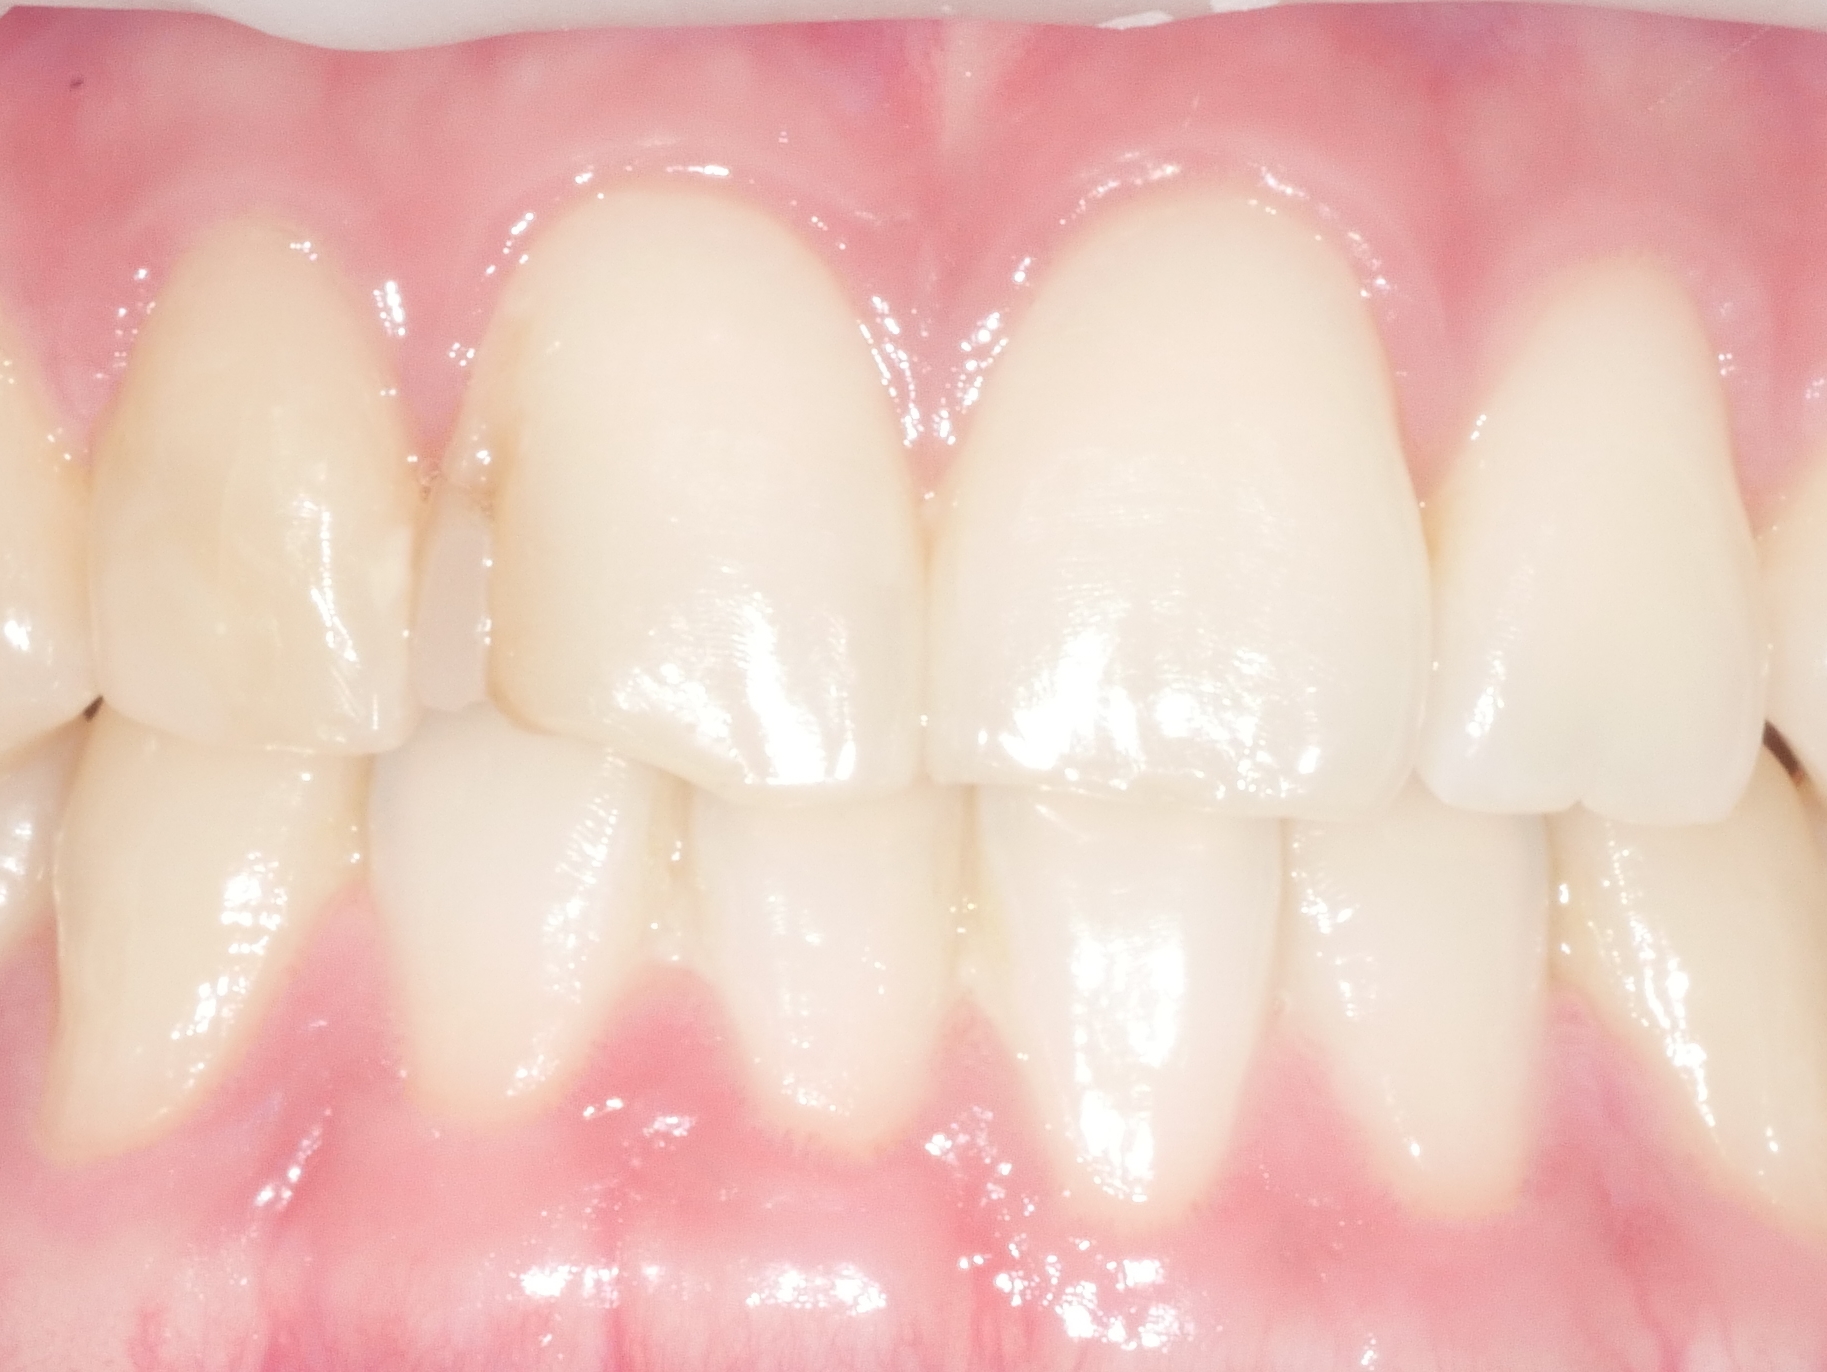

CASE.6 치아미백

치료전 2022.06.29 / 치료후 2022.07.06